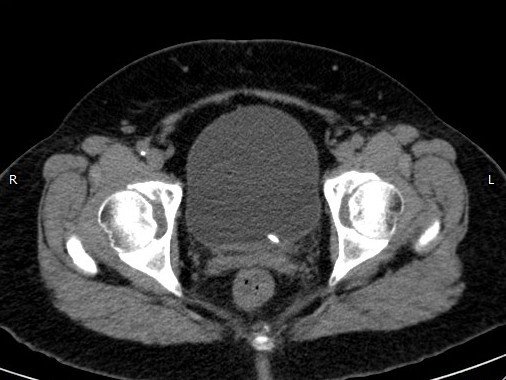

Abdominal CT images